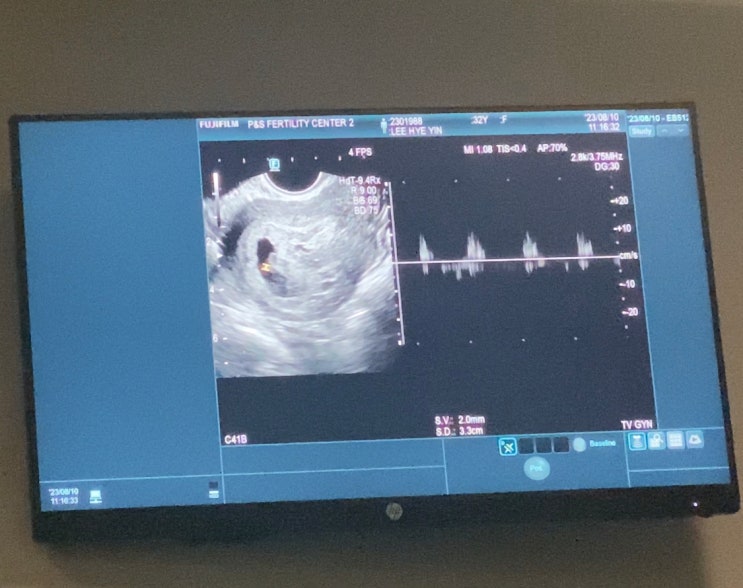

감자와눈사람 아기집 확인 / 시험관 총 비용

8/10(목) 심장소리 확인 아기집 확인 하고 1주일 만에 다시 병원 방문 이번에는 심장소리 확인하러 왔다 두...